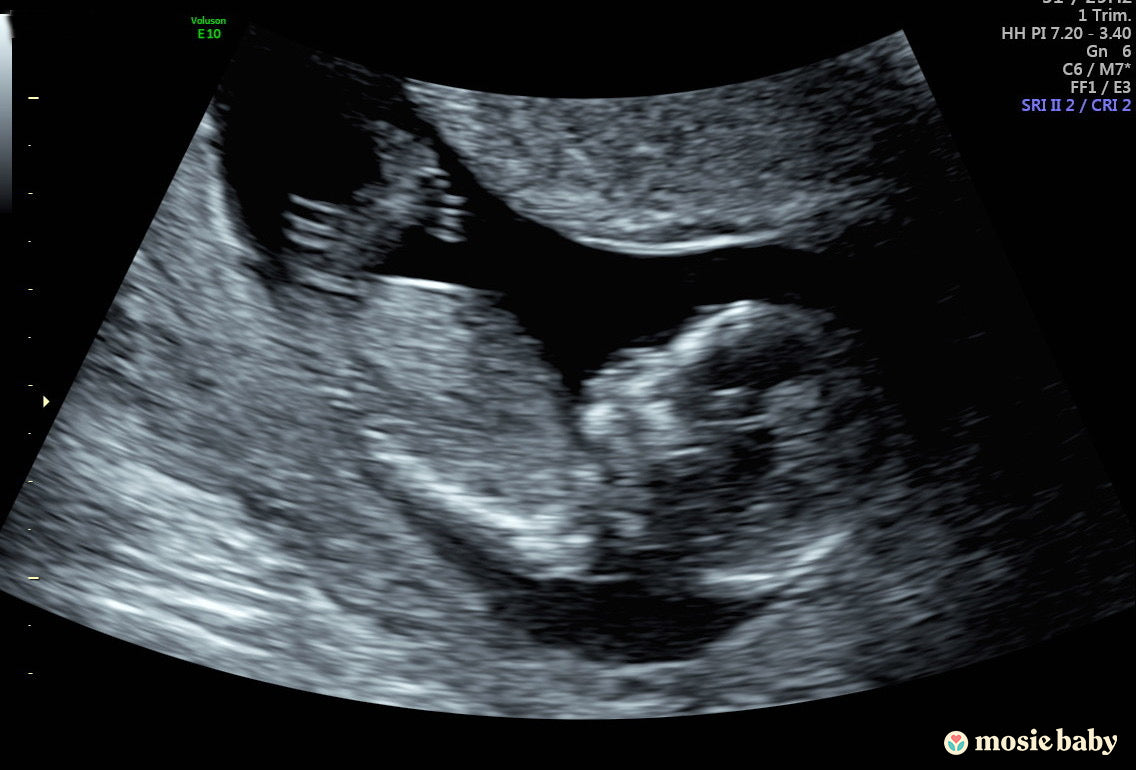

The first time using Mosie in August was not successful. I think the problem was that I didn't calculate my ovulation date correctly. At the end of September, we tried again. We tried the traditional method first, but it didn't work out very well. The next day, we used Mosie twice. I didn't expect this time to be successful because I still didn't quite trust the syringes. In about three weeks, I randomly peed on a pregnancy test strip, and I got a really faint positive result. The next few days, I tested many times using different brands, and I got them all positive. I also got positive results on my urine and blood tests at the lab. I couldn’t believe we made it with Mosie! My husband and I were so happy! Now my baby has been there for 13 weeks. We are so excited to see him/her arrive soon! Thank you Mosie!